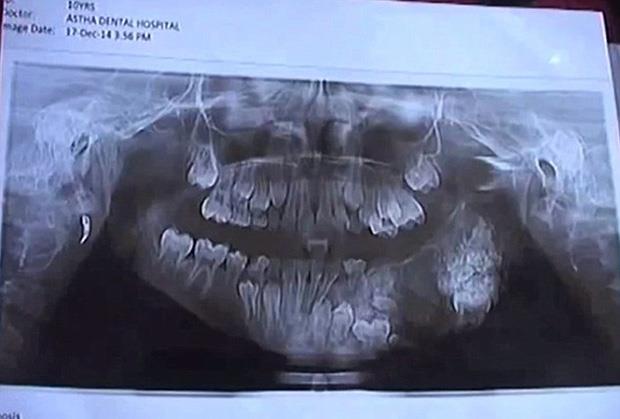

Sedmogodišnji Indijac Ašik Gavai patio je od jakih bolova u gornjoj vilici, i redovno se žalio svojim roditeljima koji su mislili da je u pitanju nešto bezazleno. Bol je postajao sve jači i jači, tako da su morali da potraže profesionalnu pomoc, piše Dejli mejl.

Sa velikim otokom na licu, došli su na pregled u lokalnu bolnicu, a njegovo stanje šokiralo je sve prisutne. Dečaku je ustanovljena neobicna dijagnoza, naime bolest koja podrazumeva specifičnu vrstu tumora koji napada vilicu i desni i izaziva pojavu dodatnih zubića koji rastu nasumice na raznim mestima u gornjoj vilici, a usledila je operacija u trajanju od 4 sata!

Operacija je uspešno obavljena u bolnici "Maharaja Yashwantrao" u Mumbaiu u Indiji."Pacijent se pojavio 5 dana pre zahvata sa gnojnim čepom i bolovima u vilici. Nakon toga isplanirana je operacija na kojoj smo odstranili 80 dodatnih zubića! Ovo je jako retko u tim godinama.", izjavili su hirurzi.

U julu 2014. godine, doktori u Indiji imali su sličan slučaj. Izveli su operaciju sličnu ovoj ali je pacijent ovaj put bio sedamnaestogodišnjak koji je imao čak 232 dodatna zuba.